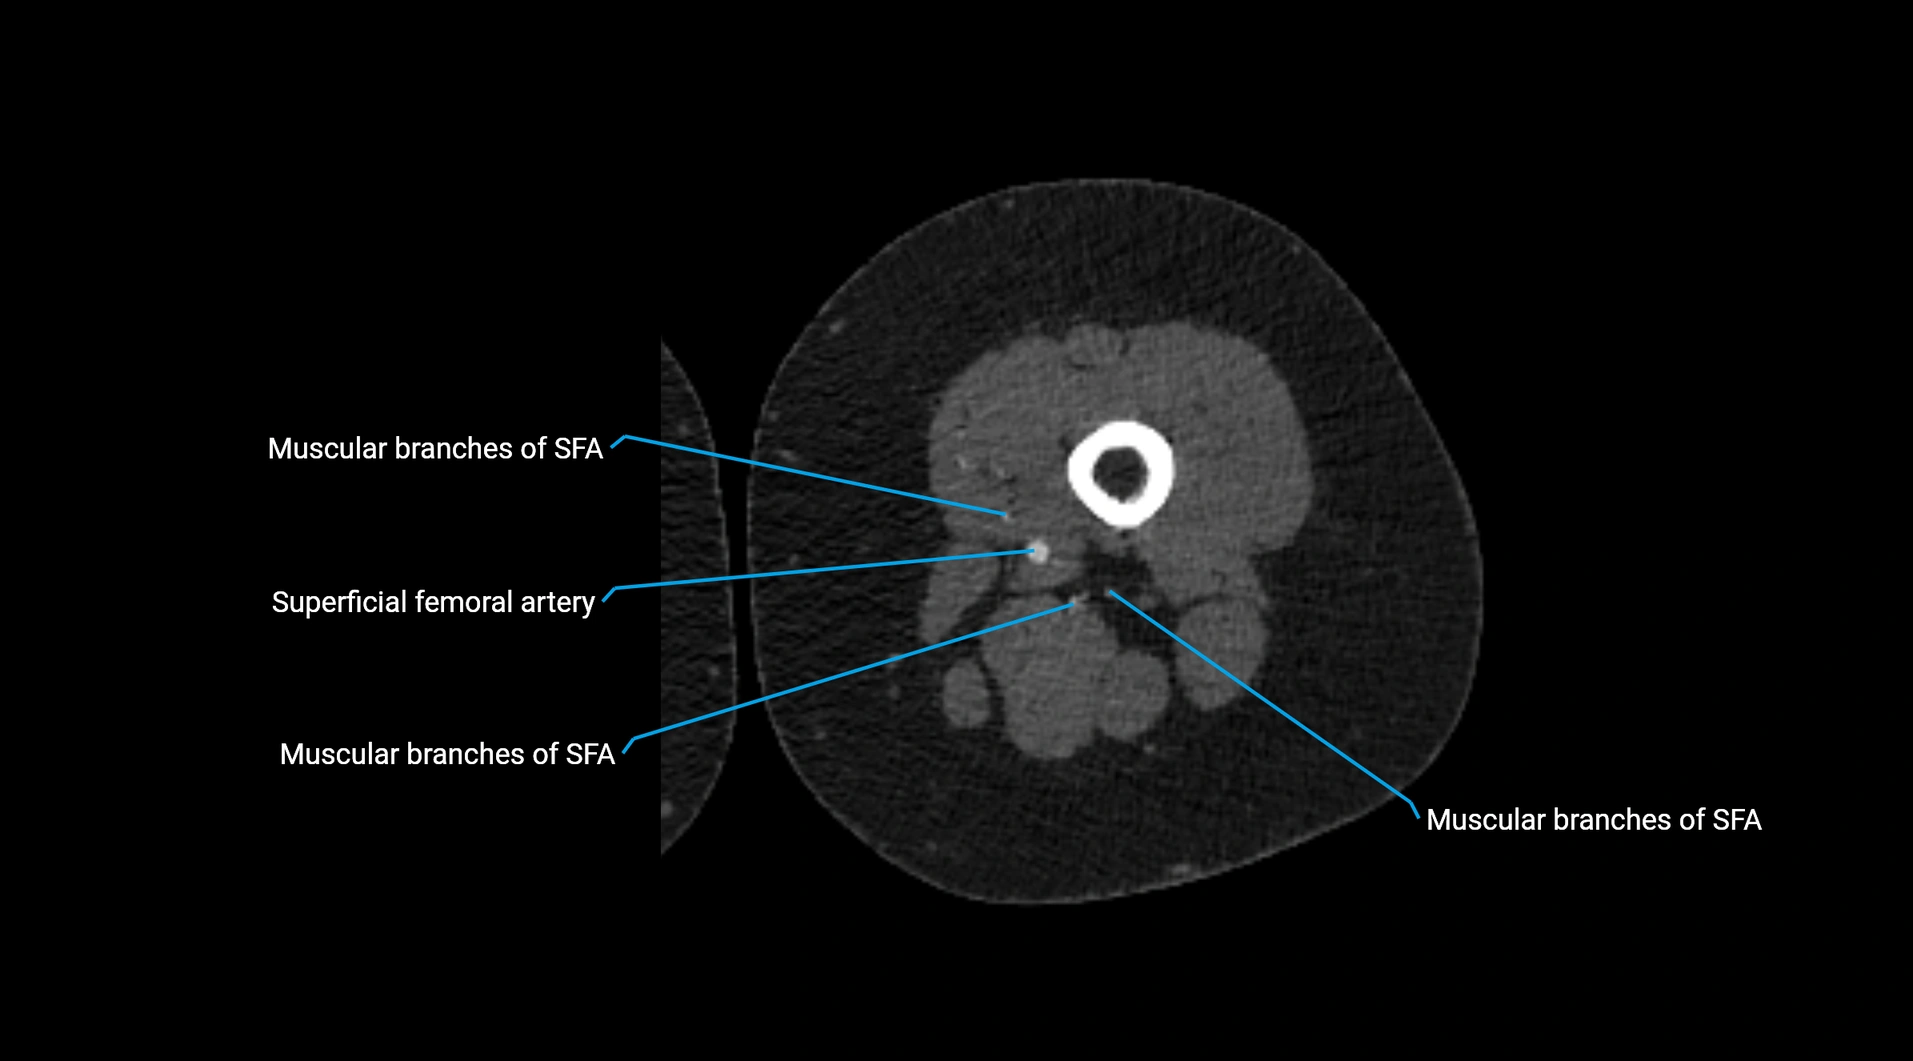

CT images

image

Contrast-enhanced CT (CTA):

• Gold standard for abdominal aortic imaging

• Provides excellent detail of lumen, wall, aneurysm, thrombus, and branch vessels

• Multiplanar and 3D reconstructions help in aneurysm measurement, stent graft planning, and dissection evaluation